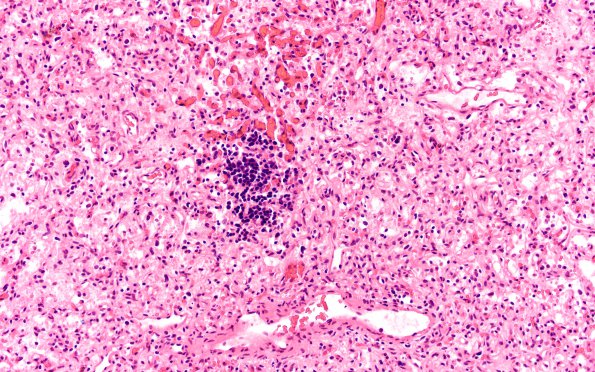

Washington University Experience | NEOPLASMS (MESENCHYMAL, NON-MENINGOTHELIAL) | Hemangioblastoma | 4B2 Hemangioblastoma (Case 4) H&E 5 EMH

4B2,3 There are small foci of extramedullary hematopoiesis, seen at higher magnification in 4B3 (H&E).